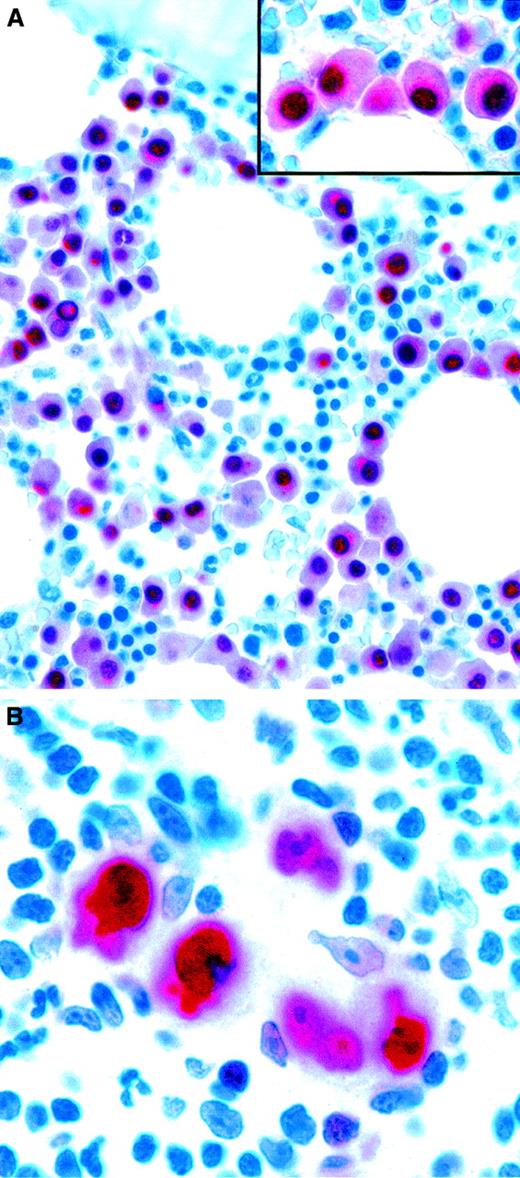

Expression of the plasma cell–associated marker MUM1/IRF4 in neoplastic lymphoid cells.

(A) Bone marrow biopsy specimen showing infiltration by multiple myeloma. Monoclonal MUM1/IRF4 is present in the nuclei and the perinuclear area in neoplastic plasma cells. Residual hemopoietic elements are unlabeled. The inset shows higher magnification-view of the same field. (B) Strong labeling of tumor cells in classic HD (APAAP technique in paraffin sections). Original magnification A, × 600; A inset, × 1000; B, × 1000.

Because of the restriction of MUM1/IRF4 to late-stage B cells, it is potentially valuable (used in combination with other plasma cell markers, such as CD138) for recognizing myelomas (Figure4A). Furthermore, its consistent expression in neoplastic cells in HD (Figure 4B) can be of diagnostic help when the staining highlights Reed-Sternberg and Hodgkin cells in a tissue biopsy specimen (eg, of bone marrow).